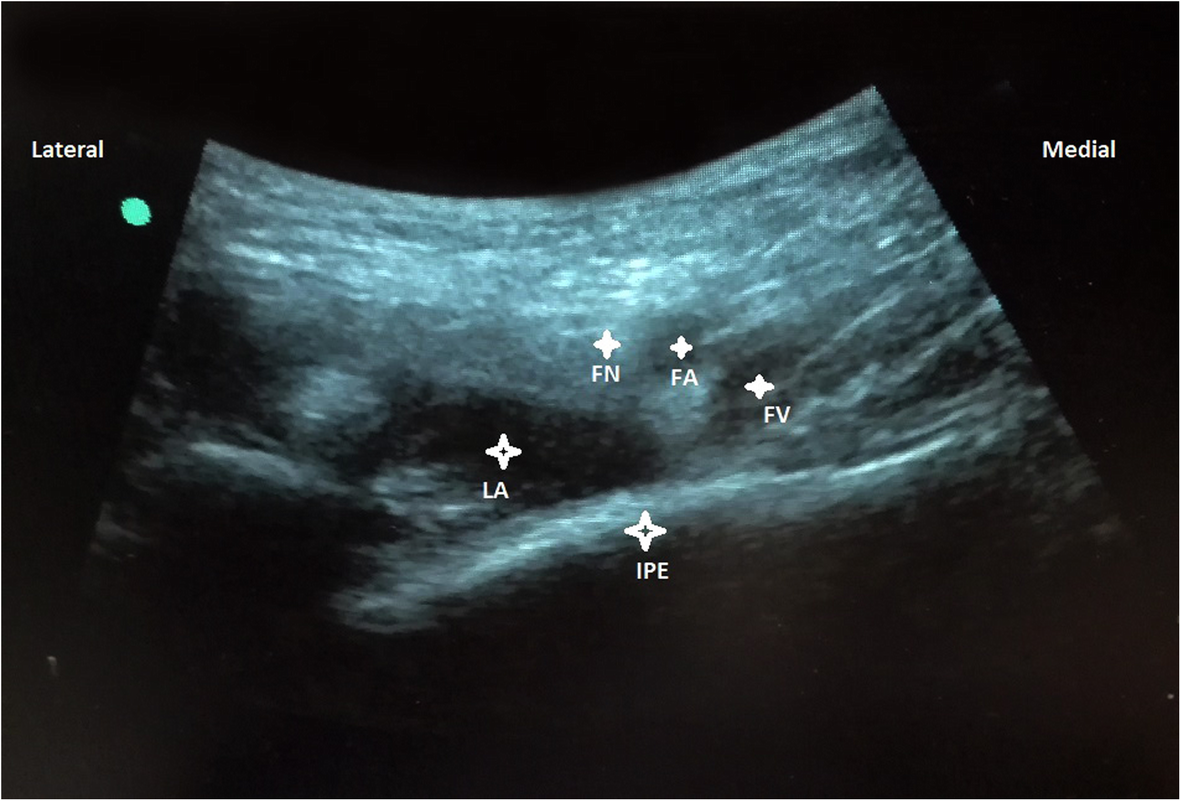

Fig. 4From: Analgesic evaluation of ultrasound-guided Pericapsular Nerve Group (PENG) block for emergency hip surgery in fragile patients: a case seriesFemoral nerve (FN), artery (FA), vein (FV), Iliopubic eminence (IPE), Local anesthetic mixture (LA)Back to article page